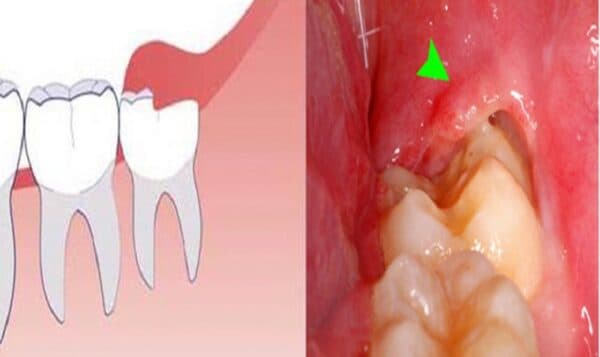

Bởi vì răng khôn thường mọc sau các răng khác, không gian trong vòm miệng thường không đủ để chúng có thể phát triển một cách bình thường. Điều này thường dẫn đến việc răng khôn mọc không đúng vị trí, xô lấn với các răng khác và gây ra cảm giác sưng, đau đớn.

Trong nhiều trường hợp, răng khôn mọc không đúng vị trí, thậm chí mọc ngầm, mọc lệch mà không được can thiệp kịp thời. Điều này có thể làm cho phần nướu xung quanh răng bị sưng tấy, tạo điều kiện để thức ăn tích tụ và gây hôi miệng, cũng như gây ra tình trạng viêm nướu.

Răng khôn mọc có thể gây ra nhiều vấn đề như viêm nhiễm và đau đớn. Răng khôn cũng có thể mọc lệch hoặc mọc ngầm, tạo ra cảm giác sưng, đau đớn trong miệng, làm cho việc nhai thức ăn trở nên khó khăn.

Trường hợp viêm nhiễm do răng khôn kéo dài mà không được kiểm tra hoặc can thiệp kịp thời có thể gây hủy hoại mô xương xung quanh răng. Tệ hơn, nó có thể tác động xấu đến cả hàm răng còn lại.